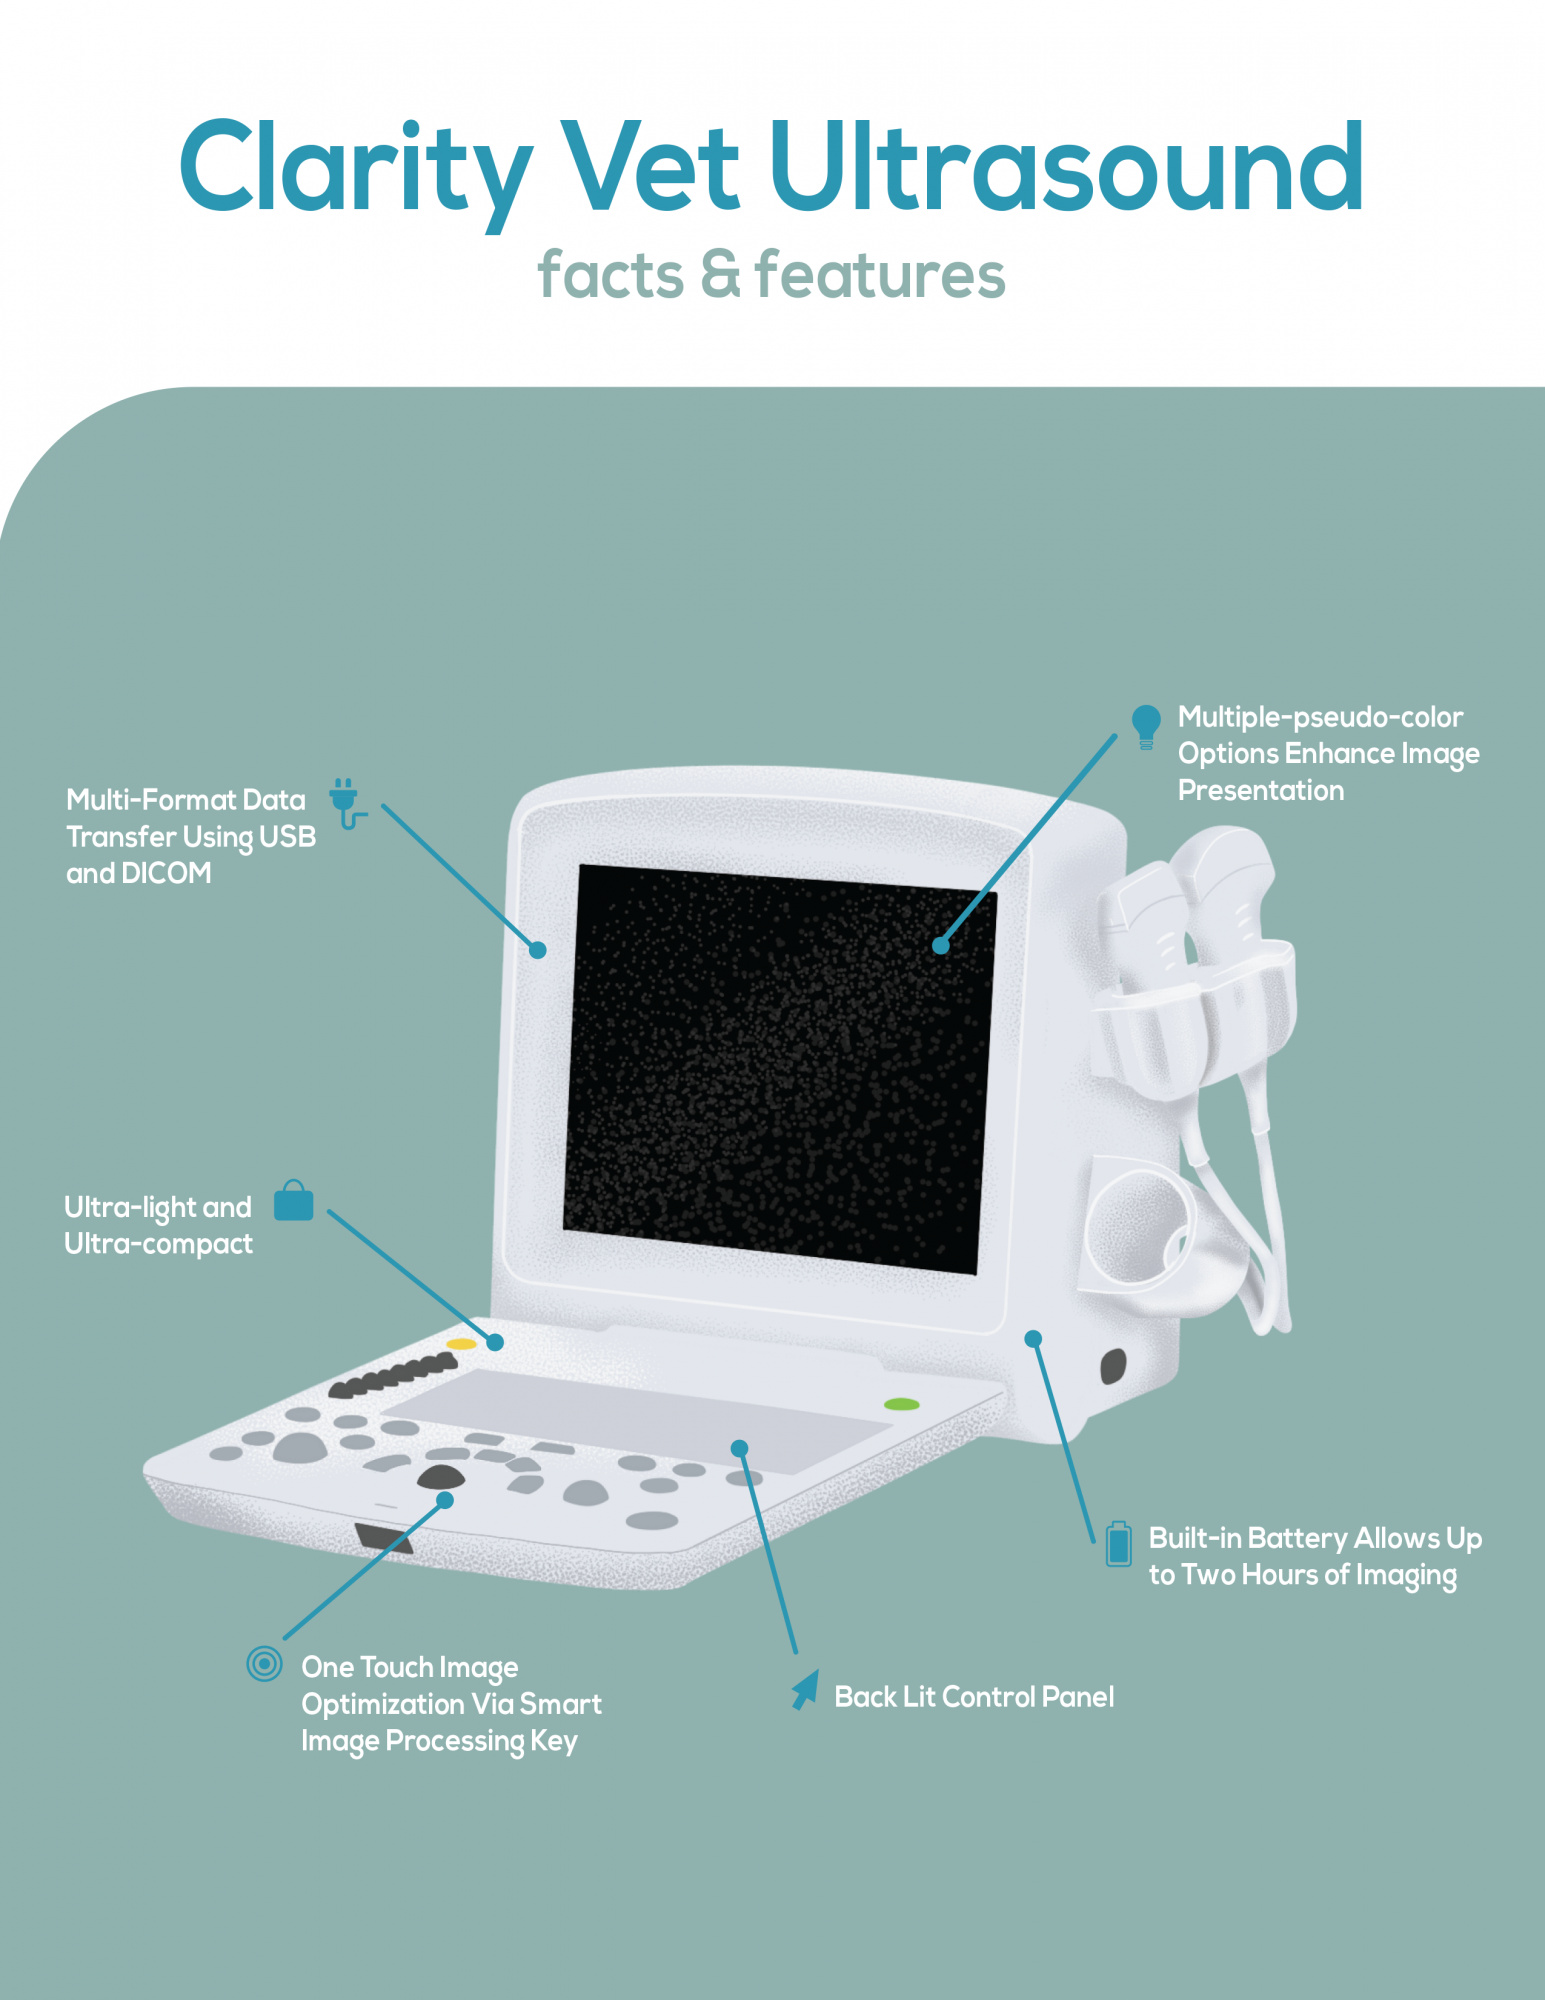

12.1″ TFT-LCD monitor

Two active and exchangeable connectors

Easy to use, backlit control panel

Multiple peripheral ports

Multi-format data transfer via USB and DICOM

Multiple-pseudo-color options enhance image presentation

One-touch image optimization via smart image processing key

Two hours of battery-powered operation